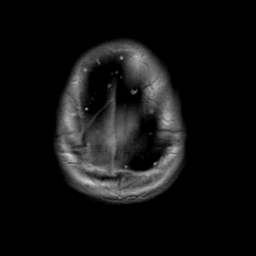

Meningioma, MR Study #2 -- Slice #20

[Home][Help][Clinical] Slice 20